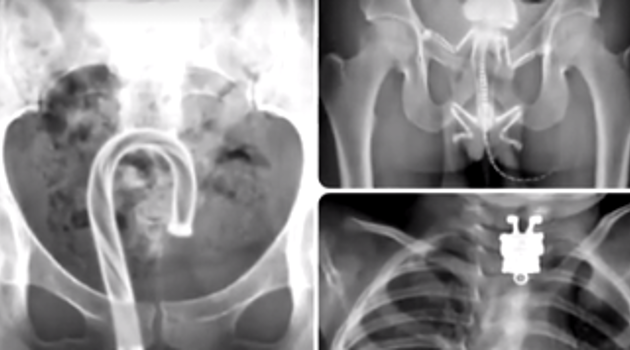

Самые странные вещи, найденные рентгеном